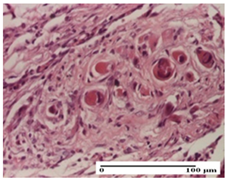

| dermal collagenization (S0, G0) | severe dermal collagenization that included the muscle layer (S1, G1) | severe dermal collagenization (S1, G0, D0) | |